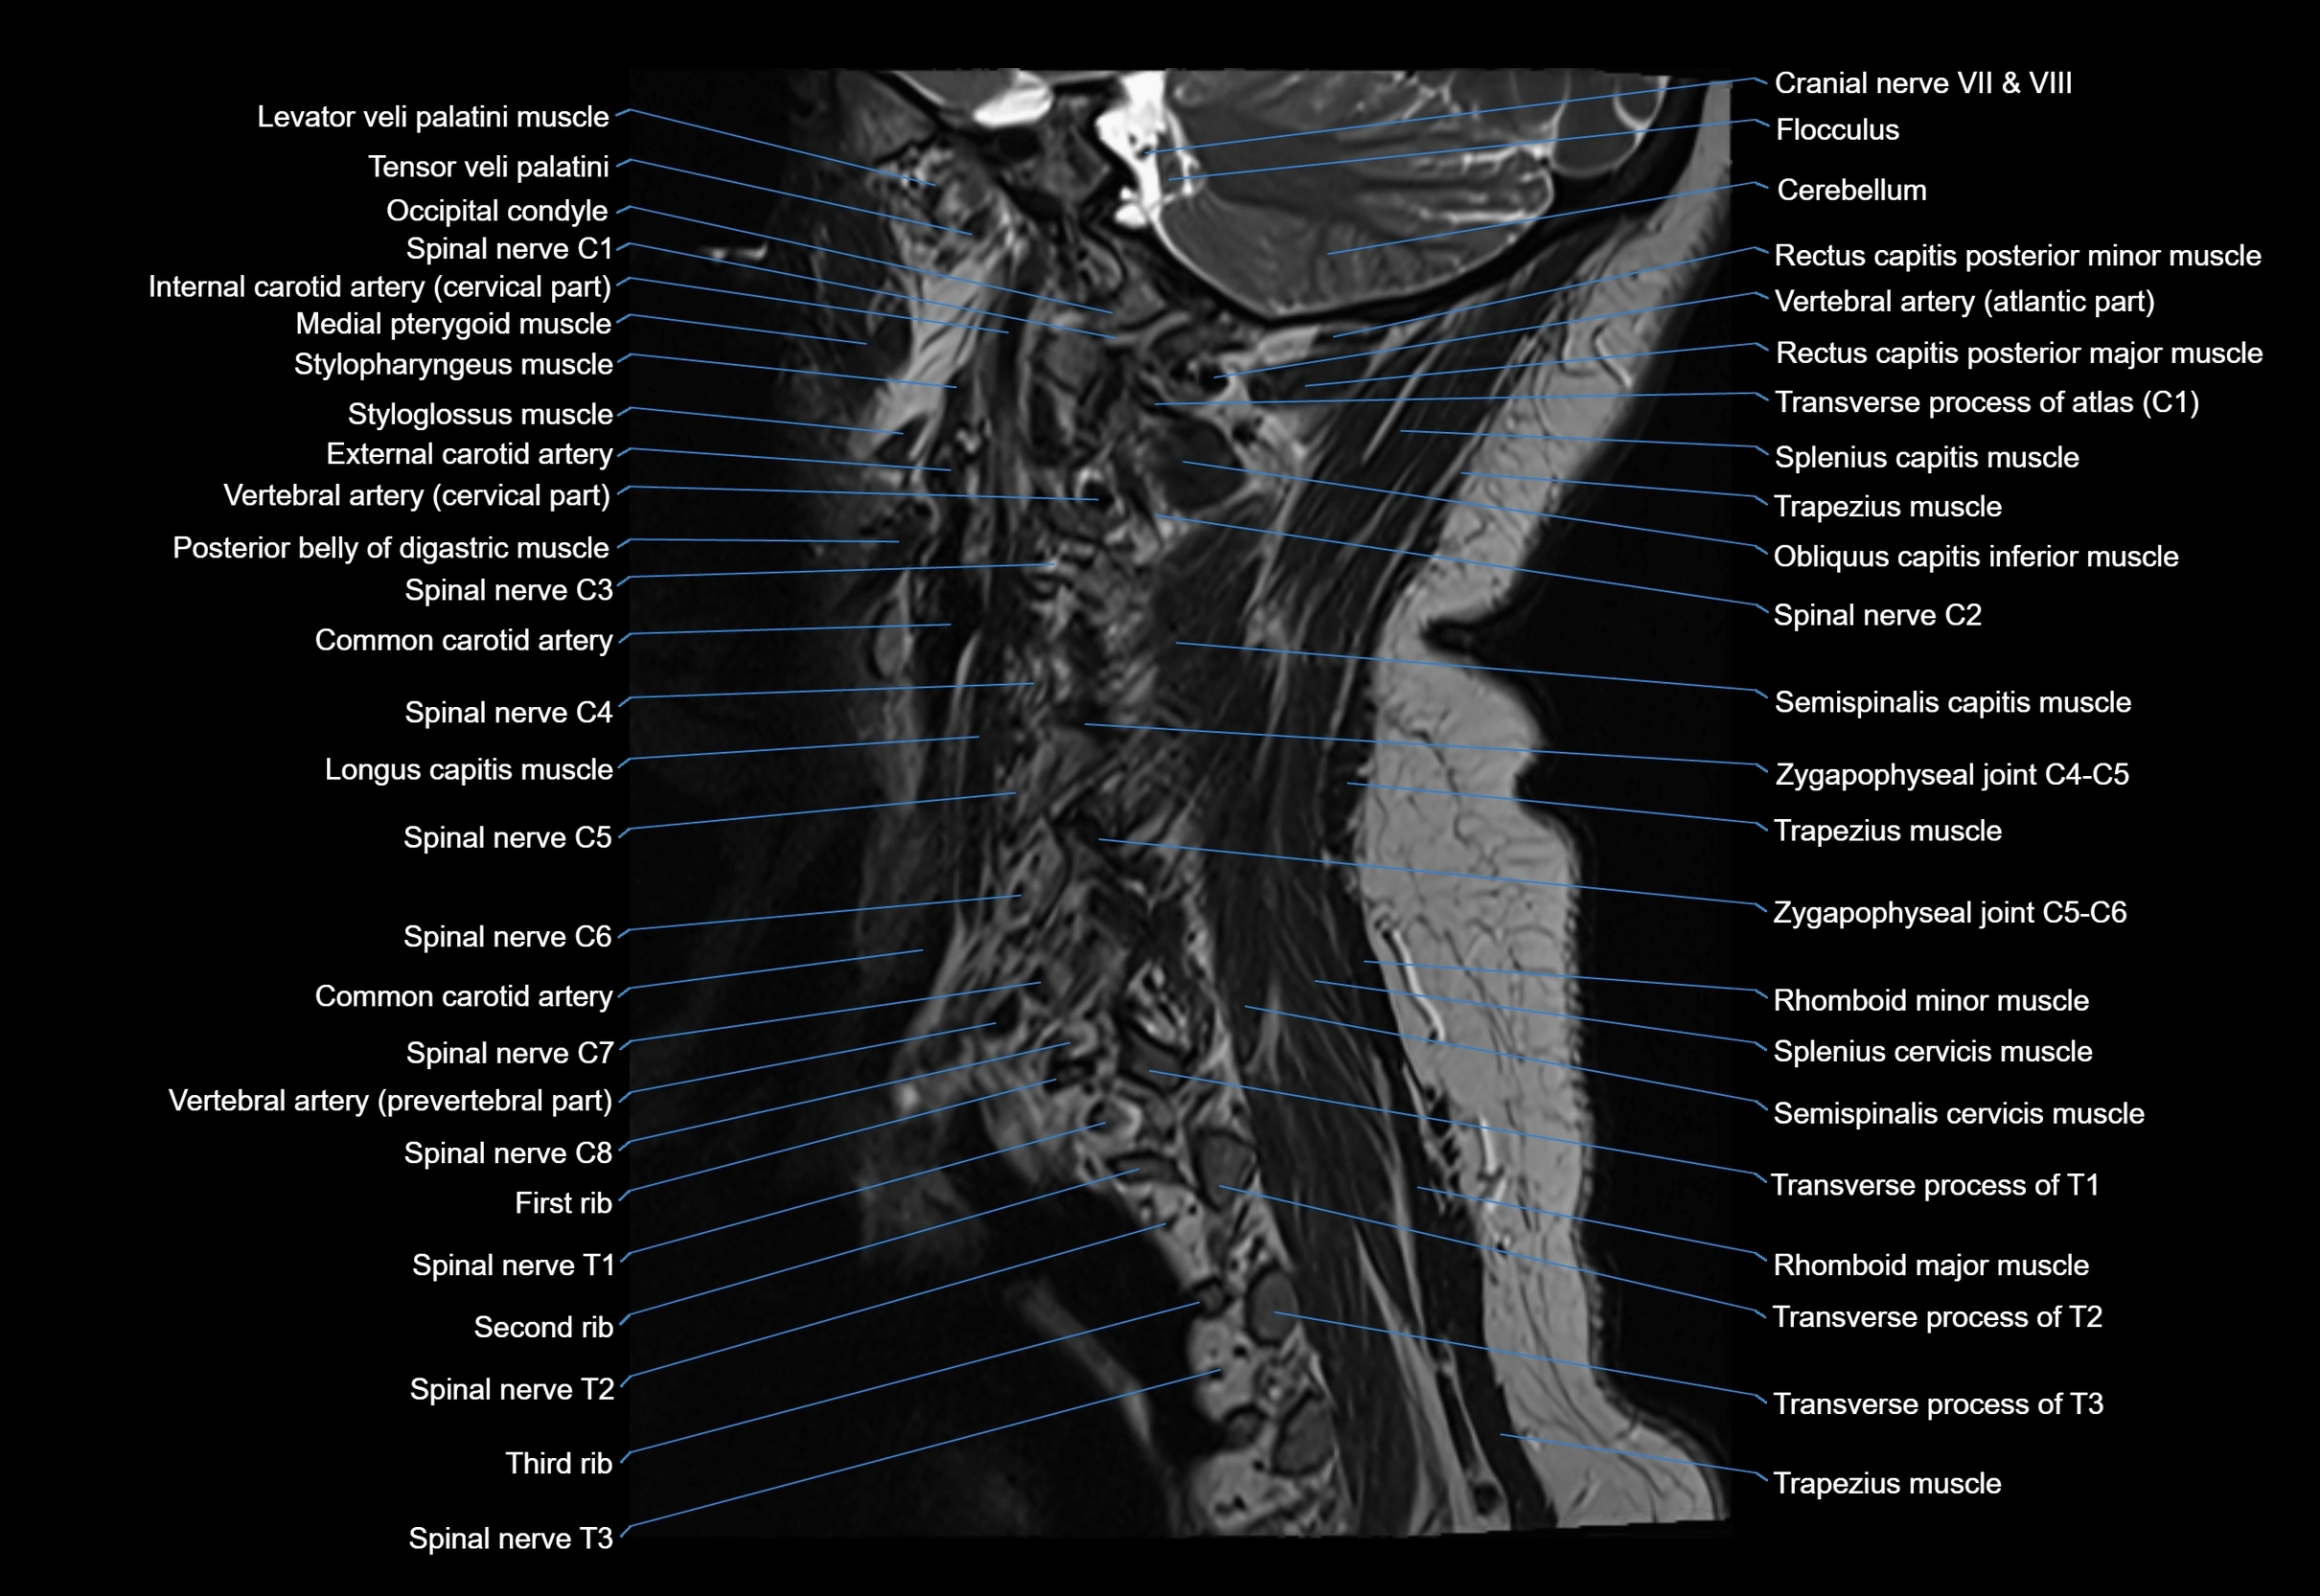

MRI appearance

T1-weighted images:

• Annular epiphysis: Low signal cortical rim at the vertebral margin

• Adjacent marrow: Intermediate-to-high signal in the vertebral body

• Disc interface: Clear delineation between bone and annulus

T2-weighted images:

• Annular epiphysis: Low signal intensity line

• Endplate cartilage (in younger patients): Intermediate signal

• Intervertebral disc: High signal nucleus pulposus

STIR:

• Annular epiphysis: Low signal cortical rim

• Adjacent marrow: Suppressed fat signal with preserved bony outline

• Utility: Highlights marrow and endplate interface in developing spine

MRI image

image